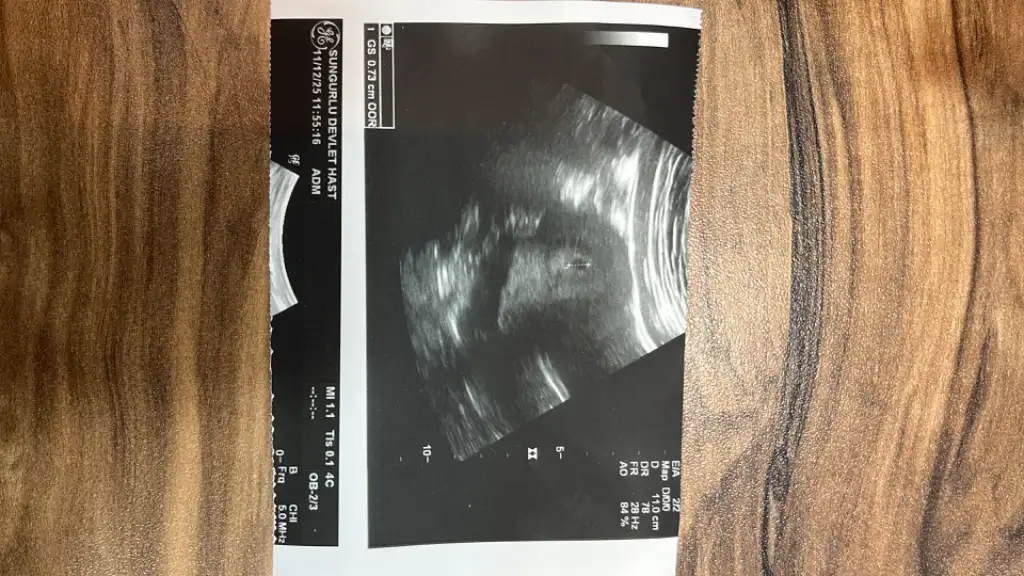

Artık resmen gebeyim kızlar duyduk kalp atışını binlerce kez şükürler olsunHerşey yolunda haftasıyla uyumlu gidiyor kan ve idrar testini tekrarladı bir tanesi 3 güne çıkarmış salı günü sonuç göstermeye gidicem kendi doktoruma bulamadım randevu ama başka bir doktorda görebilir dediler bekletmeden göstercem

Arkadaşlarkeseyi gördüm ben de

Çok heyecanlıyım kan ve idrar verdim çıktım nasıl mutlu oldum doktor da beklemiyordu önce adet tarihimi sordu sonra dedi ki direkt sen 2 hafta sonra gel dedi ben de üzüldüm yine de bakalım bi dedi ultrasonla umutsuz bir şekilde bi baktık ki benim pirinç tanemin kesesi varhemen beni alıp kayıt ettiler gebe okuluna falan bi yerlere çağırdı öğleden sonra

Ayy hadi gözün aydın sağlıcakla kucağınaalmak da nasip olsun inşallahArkadaşlarkeseyi gördüm ben de